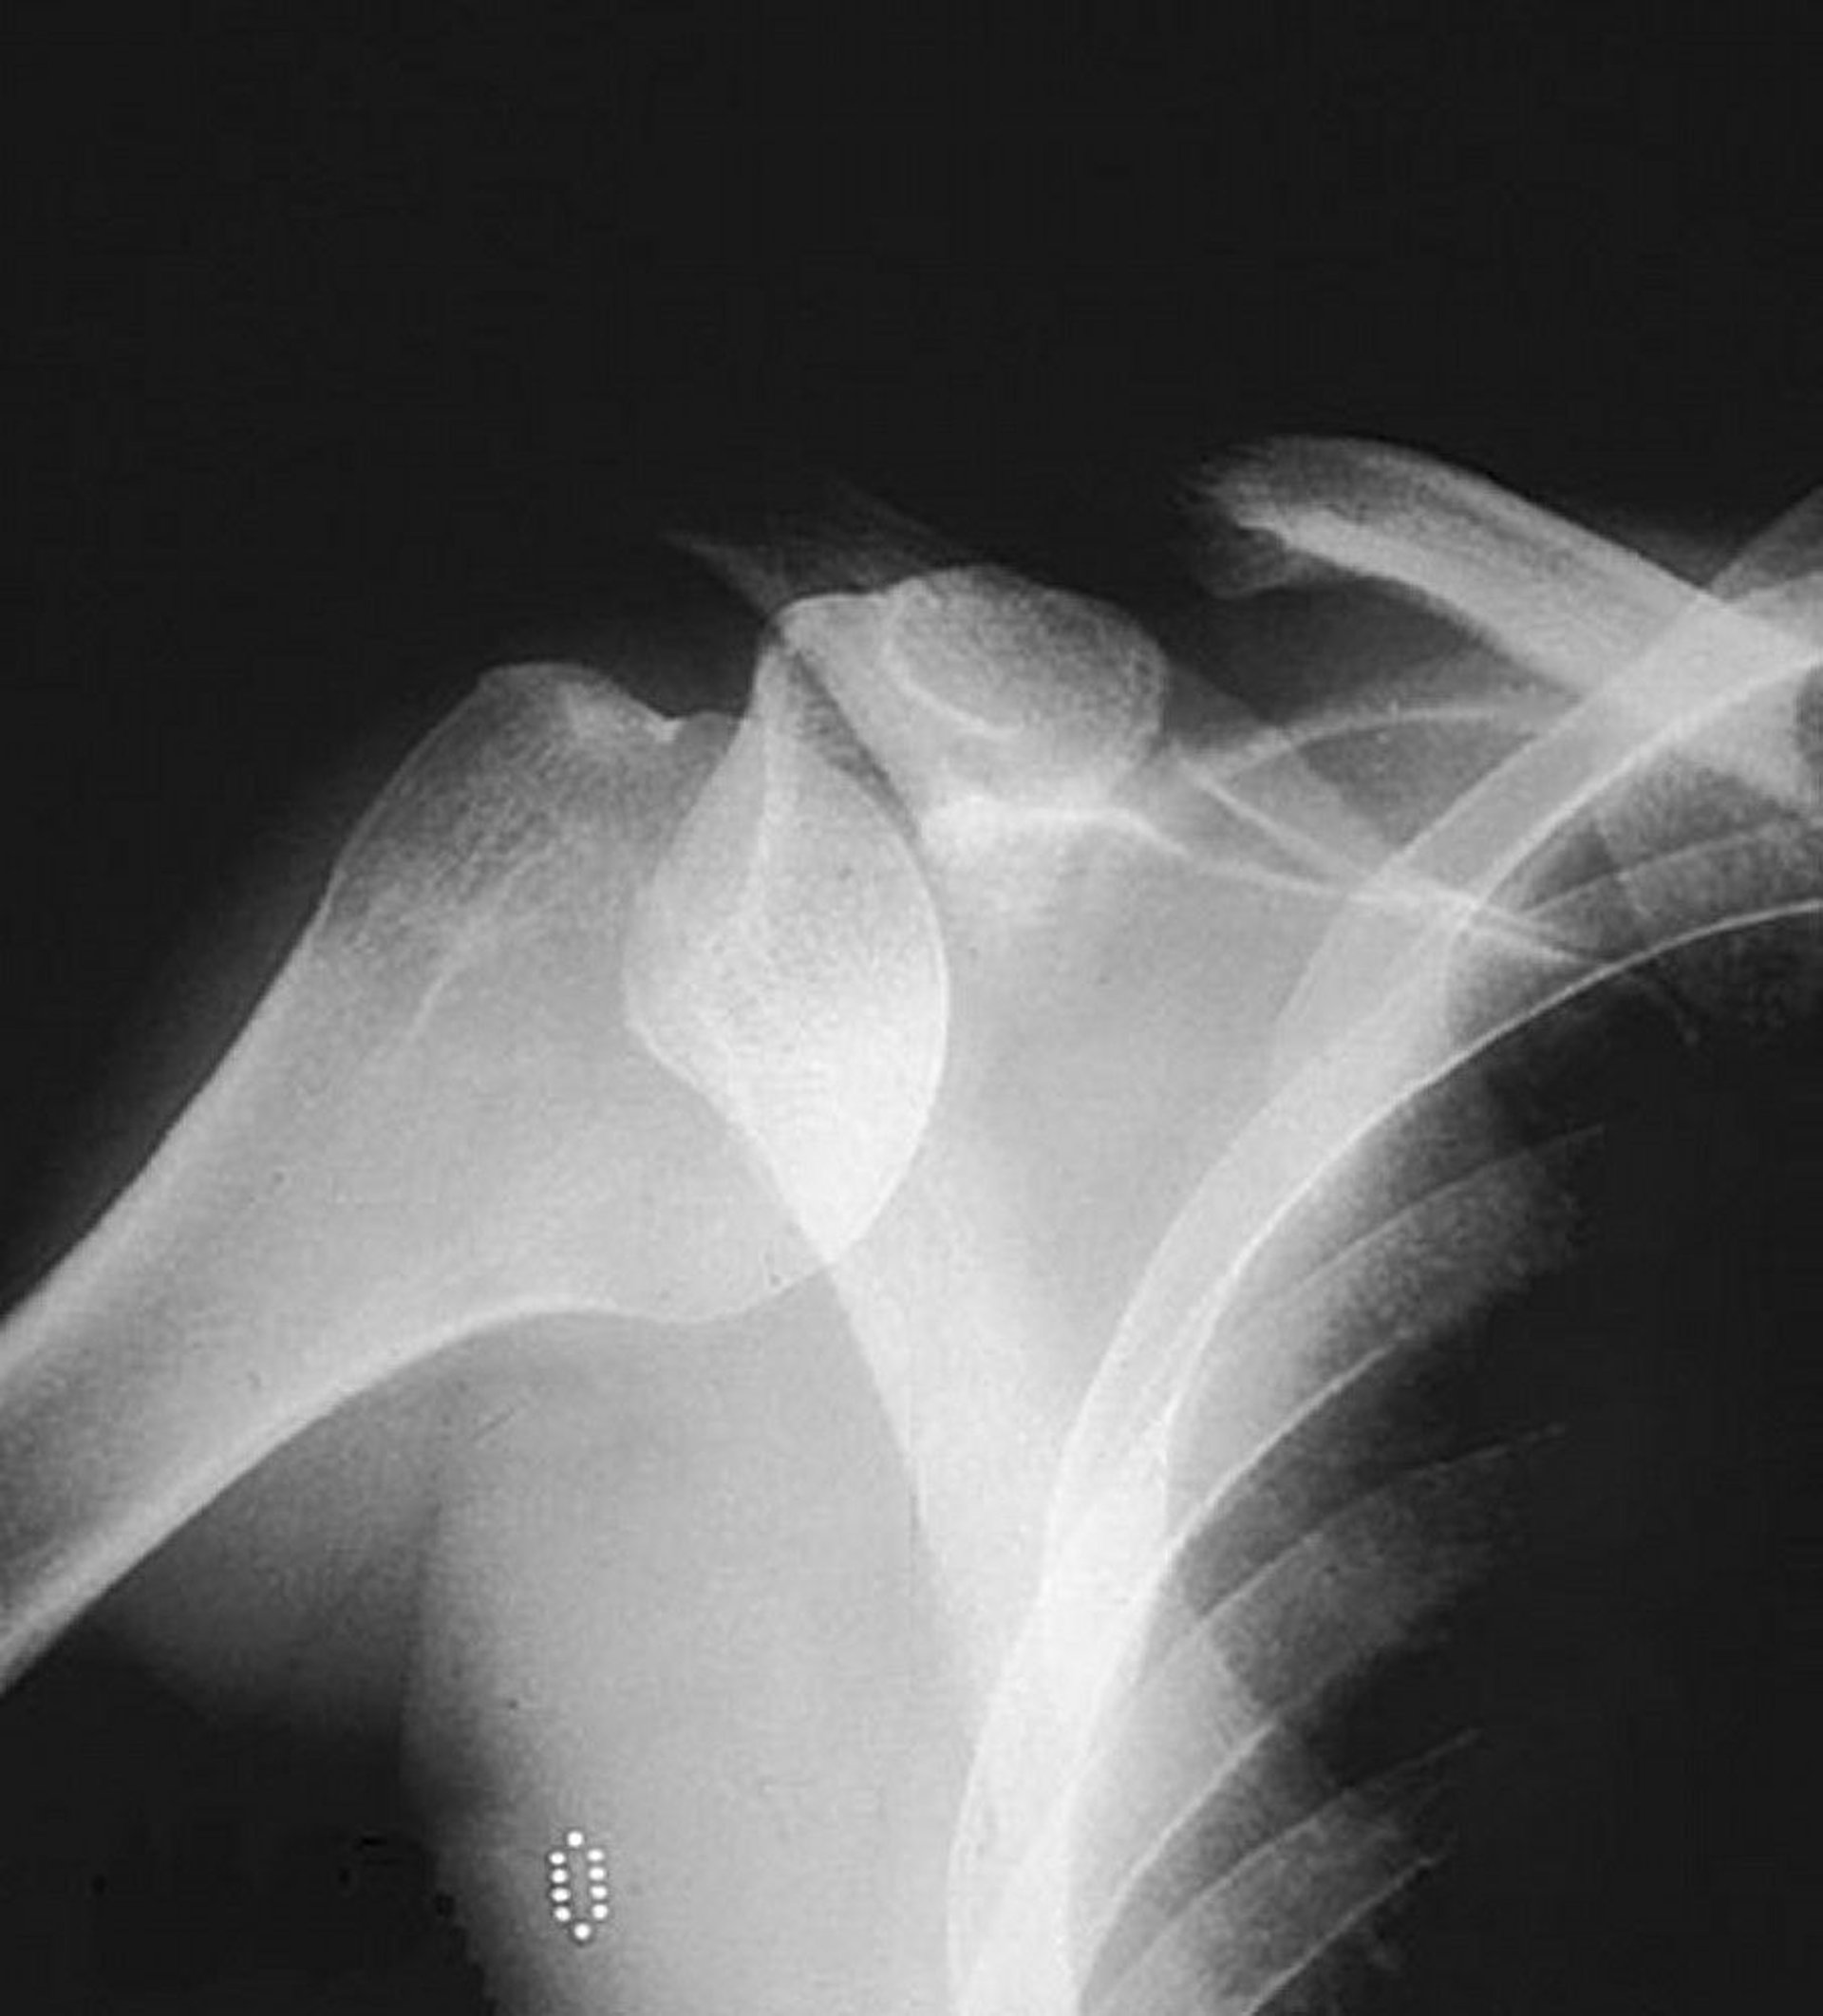

Anterior Glenohumeral (Shoulder) Dislocation

An anteroposterior plain radiograph shows the humeral head out of its usual location within the glenoid fossa, suggesting an anterior dislocation.

By permission of the publisher. From Jacobs P: Current Orthopedic Diagnosis and Treatment. Edited by JD Heckman, RC Schenck, and A Agarwal. Philadelphia, Current Medicine, 2002.